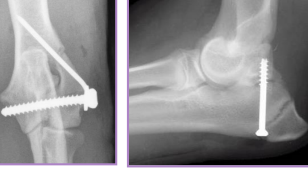

Tension Band Wiring

primary distractive forces

Why: Converts distractive into compressive forces

Patellar, Traction physeal, Olecranon fractures, Tibial crest avulsion

What: Kirschner wires + figure-of-eight cerclage wire (18-22g)